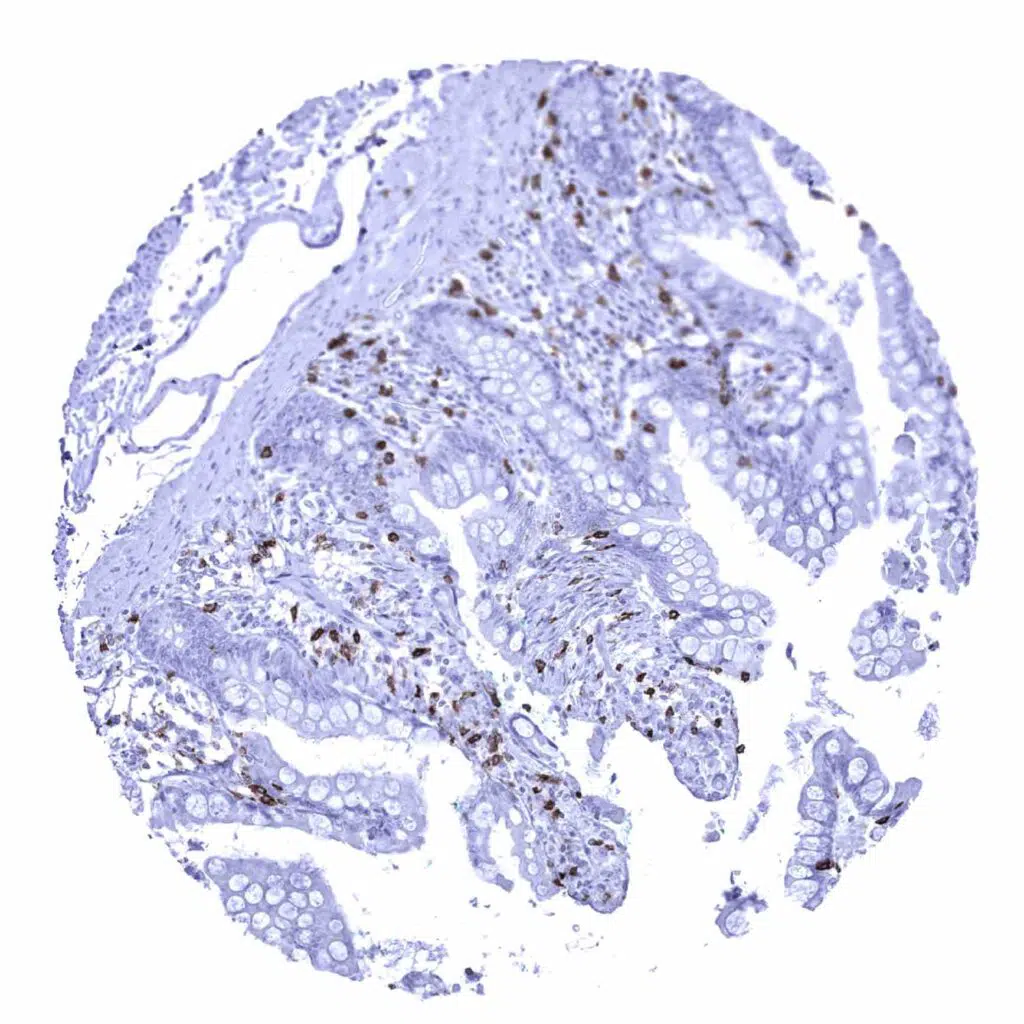

Esophagus - Adenocarcinoma containing numerous CD8 positive lymphocytes